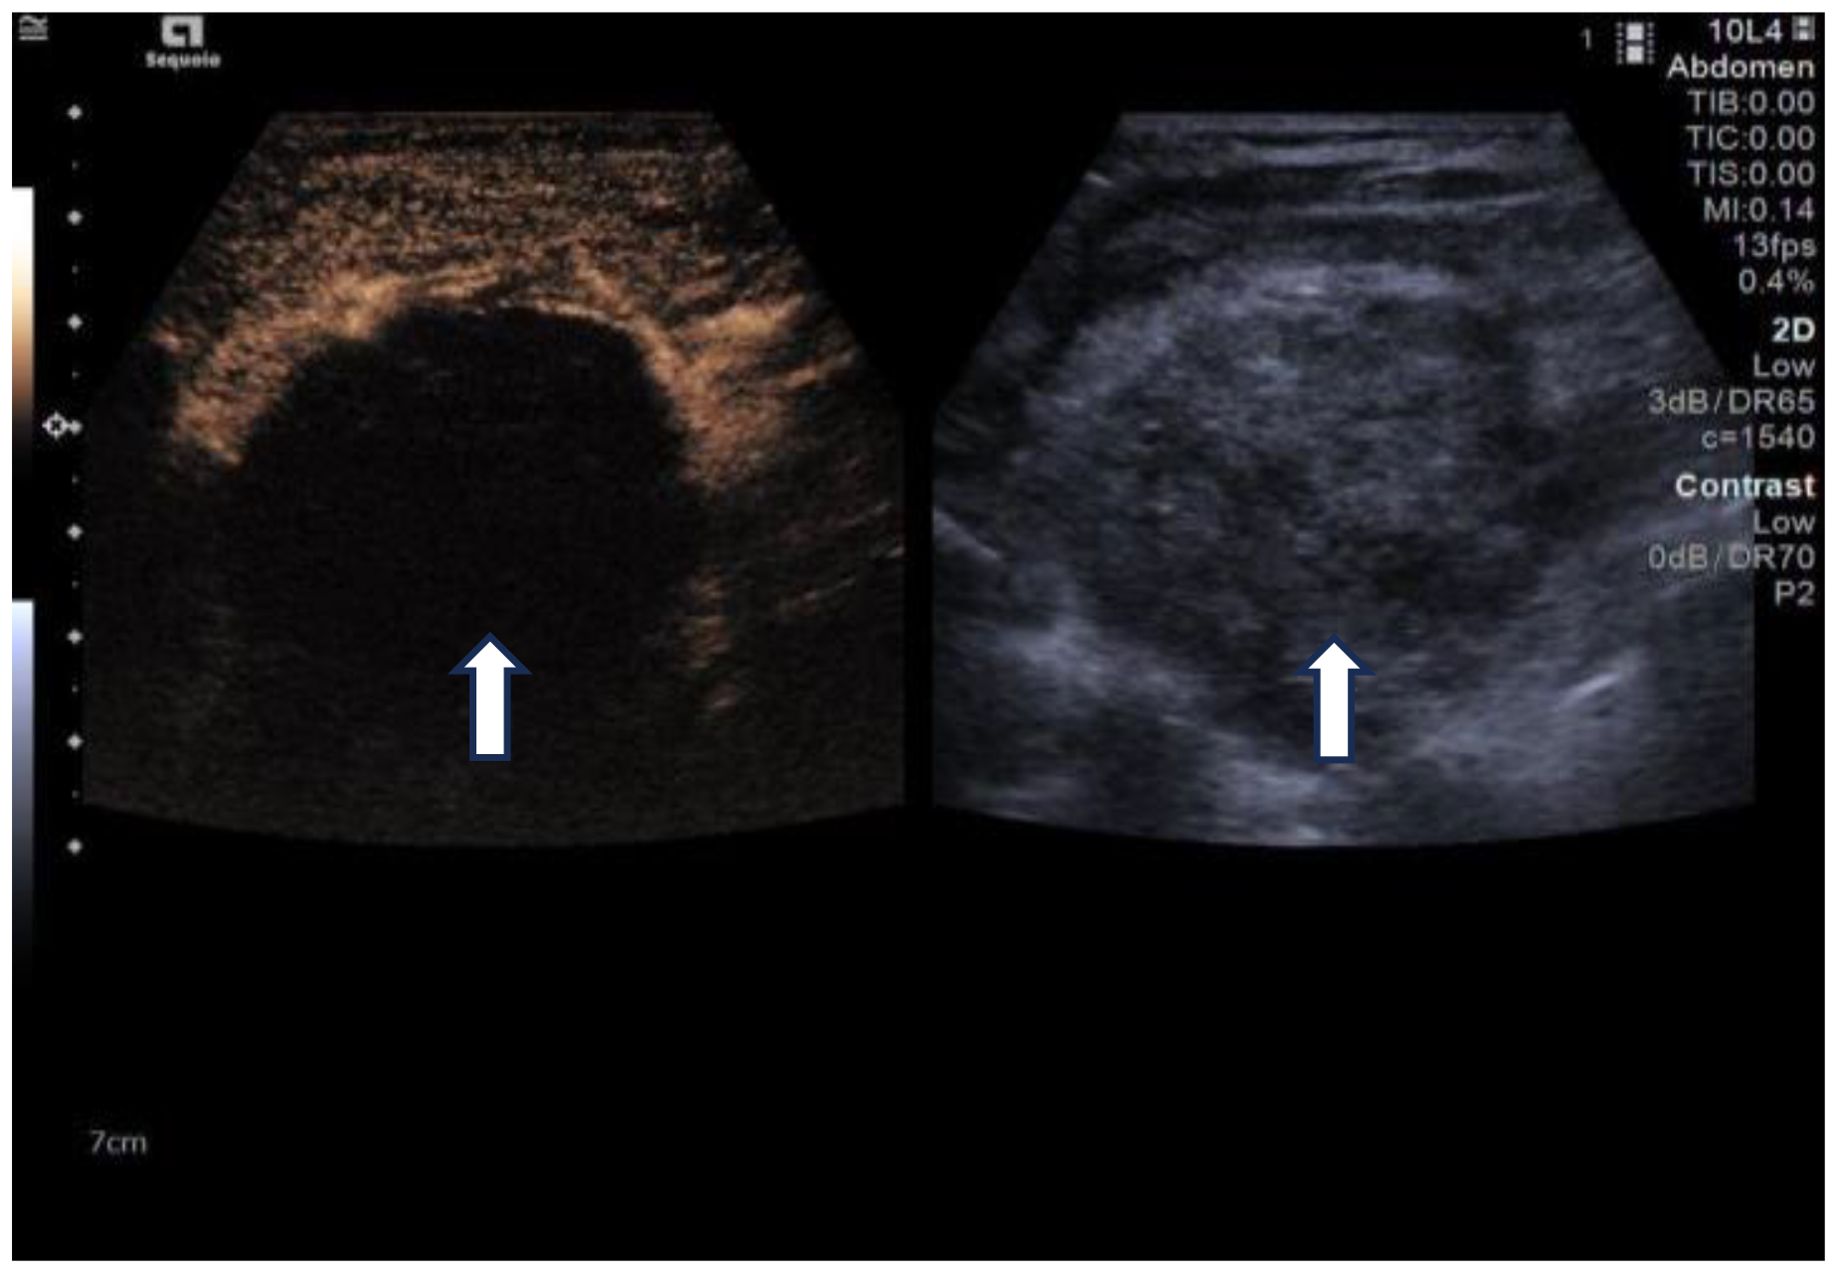

Due to her prior thyroid surgery and strong preference to avoid further surgery, the patient strongly requested a non-surgical treatment approach. After a thorough discussion, we performed an ultrasound-guided fine-needle aspiration biopsy (FNAB), which yielded a Bethesda III lesion and negative for BRAF gene. Based on the clinical and imaging examination, we opted for ultrasound-guided radiofrequency ablation (RFA) as the treatment modality. Before the ablation treatment, contrast-enhanced ultrasound (CEUS) showed that the nodule’s enhancement pattern was similar to the surrounding thyroid parenchyma, with synchronous enhancement and regression. After disinfecting the neck and spreading a towel, local infiltration anesthesia was applied, followed by injection of 30 ml of saline into the anterior and posterior spaces of the left thyroid and the paratracheal space under ultrasound guidance and real-time monitoring, and an isolation zone was formed around the giant nodule in the left lobe (Figure 3), and the thickness of the zone was ≥5 mm. Once an adequate isolation zone was established, the RFA needle (needle type: using an internally cooled 18G electrode, 10cm in length, and with a 10mm active tip size, powered by the RF generator (AJ-500A, Angel Medical))was inserted near the posterior aspect of the mass, and ablation commenced. The procedure was performed in a stepwise manner, retreating and adjusting the needle path to ensure complete treatment from the deep to the superficial portions of the nodule. The procedure lasted 20 minutes and 53 seconds at a power of 60W. While strong echogenicity on 2D ultrasound indicated near-complete ablation, residual contrast enhancement on CEUS suggested a small untreated area. Additional ablation was performed until both 2D ultrasound and CEUS confirmed complete lesion necrosis. The total ablation time was 25 minutes and 20 seconds. Throughout the procedure, the patient remained conscious and communicative, allowing continuous assessment of her vocal function. Vital signs, oxygen saturation, and ECG were monitored to ensure procedural safety. The patient experienced only mild neck discomfort and no complications such as bleeding or dyspnea. One month after the procedure, ultrasound of the patient’s follow-up showed a hypoechoic region at the ablation site with “black hole” changes on CEUS, indicating effective necrosis (Figure 4). Postoperative thyroid function remained normal, vocal function was preserved, and the patient expressed high satisfaction with the cosmetic outcome, especially the absence of a surgical scar.

Figure 4. One-month follow-up after ablation. Left: Changes of the “black hole” on CEUS, Right: 2D ultrasound. (white arrows).